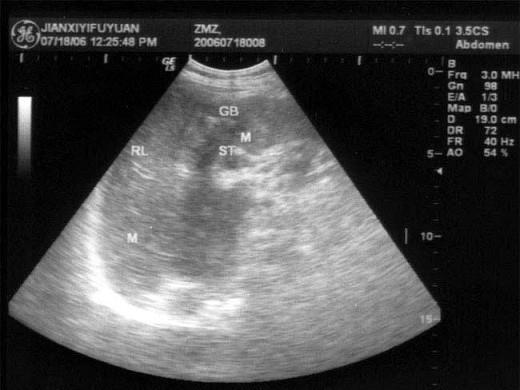

问题 患者男46岁,既往有胆囊结石病史,上腹部疼痛不适年余,加重1个月,皮肤、巩膜轻度黄染,B超检查如图所示,根据超声声像图,诊断为?(?)

选项 A.胆囊结石并胆囊炎,肝血管瘤 B.胆囊结石并胆汁淤积,肝血管瘤 C.胆囊结石并胆囊癌,肝转移性癌 D.胆囊结石并肝癌 E.胆囊结石并胆息肉,肝转移性癌

答案 C